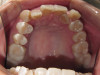

Cosmetic